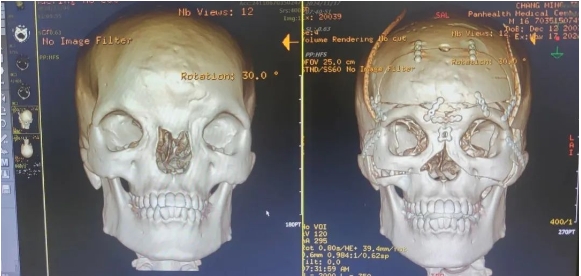

術(shù)前,整形外科劉斌團隊聯(lián)合醫(yī)院影像中心,為初晨完善顱頜面部CT三維重建,進行全面評估。為精準的測量截骨量以防止術(shù)后復(fù)發(fā)和矯正不足,劉斌團隊選擇利用計算機輔助技術(shù)模擬多次切割,來設(shè)計精準的截骨線,從而避免可能出現(xiàn)的遠期并發(fā)癥,并達到確切的美學(xué)效果。

手術(shù)非常順利,術(shù)后CT影像診斷報告顯示(如下圖),手術(shù)效果非常好,初晨兩眼骨性距離縮短至27mm,已在正常男性眼距范圍內(nèi)。